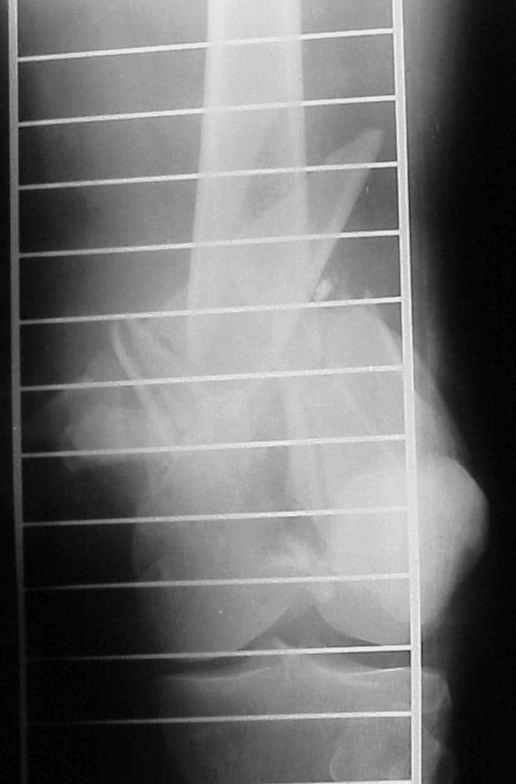

On Thersday afternoon he was alright, he is a very active man and he was moving well both knees. Later that evening he told me that while he was a little bit asleep he turned on the bed and felt pain and that the femur was loose. Here are the X-rays we took.

In this case, the fixation might have failed because of inadequate purchase of the side plate to the shaft. I say this because the initial lateral xray shows that the plate seems to be fairly anterior to the mid-axis of the femoral shaft. Once the plate pulled off of the shaft, it continued to pull out of the distal segment. With the short unicortical screws used for shaft fixation, it is imperative that the plate be applied precisely at the midline (widest diameter) of the femur. If it is applied even slightly anterior or posterior to the midline, the screws just don¹t engage the cortex. You can¹t tell by feel, since the screws lock firmly into the plate.

A second "pearl" is to place at least one or 2 lag screws between the condyles for intrafragmentary fixation before applying the LISS. Although screws were used across the coronal plane (Hoffa) fracture, I do not see any lag screws from lateral to medial. The LISS screws are designed to maintain the reduction of the distal femoral condylar mass to the shaft, but they do not function as lag screws. The intra-articular portion of the fracture demands open reduction and rigid internal fixation according to established

Condyles have separated. Would separate (peripheral ? 3.5mm, lag screws, medial to lateral or lateral to medial outside LISS footprint) lag screws have been helpful? Intercondylar fracture needs open reduction and good interfragmentary compression.

LISS is a bit proximal, and screws are not parallel with joint line. Is there excessive valgus on appropriate AP views? You might want to check the mechanical axis using electrocautery cord stretched across knee, from center of femoral head to middle of talus.